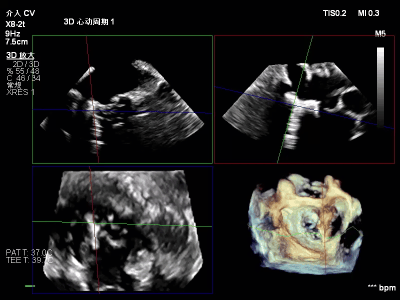

【术中操作(含关键步骤超声)】

鉴于患者术前心功能差、多支架植入的特殊情况,手术全程需兼顾“精准操作”与“保护心功能”双重要求:在全麻与经食道超声的协同引导下,团队先突破心功能受损导致的术野稳定性难题,稳步经心尖建立手术轨道与输送鞘;随后聚焦二尖瓣2偏3区精准置入一枚Ⅱf型夹合器,成功攻占这一解剖位置深、毗邻结构敏感、容错率极低而操作难度陡增的区域。

手术中,主刀术者常青教授稳定发挥,经过严谨的策略思索,挑战超精细微调整与瞬间捕获夹合,逐步逆转反流症状。从显著改善到最终完全消除,全程仅约25min的导管操作时长。在高危病例的严苛挑战下,凸显了团队操作的娴熟度与安全性。

术前术后反流对比

【术后一周复查心超提示】二尖瓣钳夹术后,二尖瓣反流(轻度),夹合器固定,瓣口呈双孔结构,内外侧孔分别见微量反流,反流束VC分别 0.15cm、0.18cm,估测有效瓣口面积约2.5c㎡,舒张期瓣口前向最大血流速度 1.2m/s,平均压差3mmHg,左室射血分数(EF)值提升至35%,心功能显著改善。目前患者已顺利康复出院。